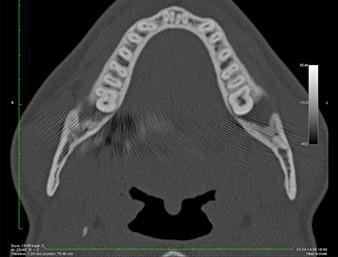

En la imagen en 3D (tomografía volumétrica digital) se constató que el resto radicular se encontraba muy desplazado en sentido distocaudal en la transición situada entre la porción horizontal y la ascendente del maxilar inferior (figura 2).